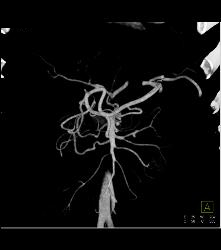

Median Arcuate Ligament Syndrome Collaterals